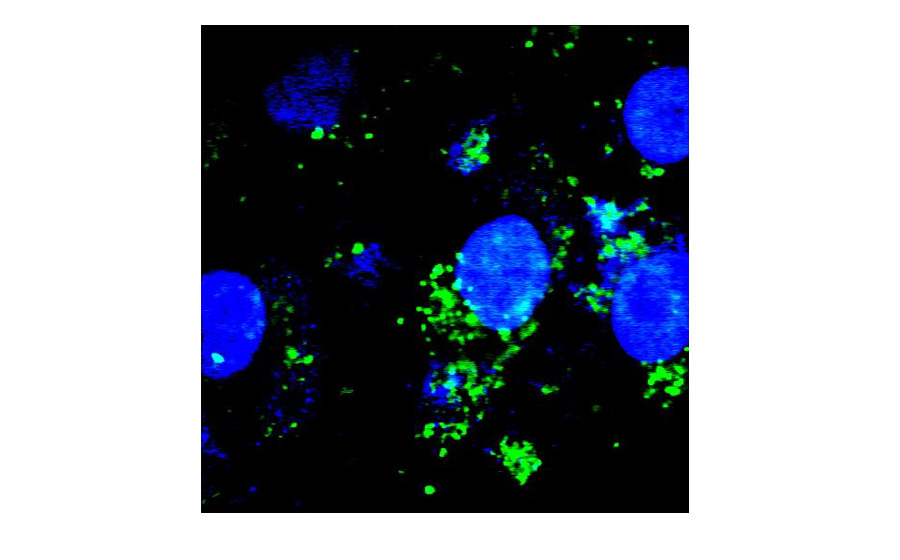

Pharmacodynamics

Whether the drug particle is correctly uptake by the target cell is critical evidence in pharmacodynamics. Through the optical sectioning capability of JadeBio, we can easily indicate the uptaking when showing the overlapped images once we label the cell and the drug particle in different colors. Furthermore, through high-resolution imaging of JadeBio, we can investigate which organelle is interacting with the drug particles.